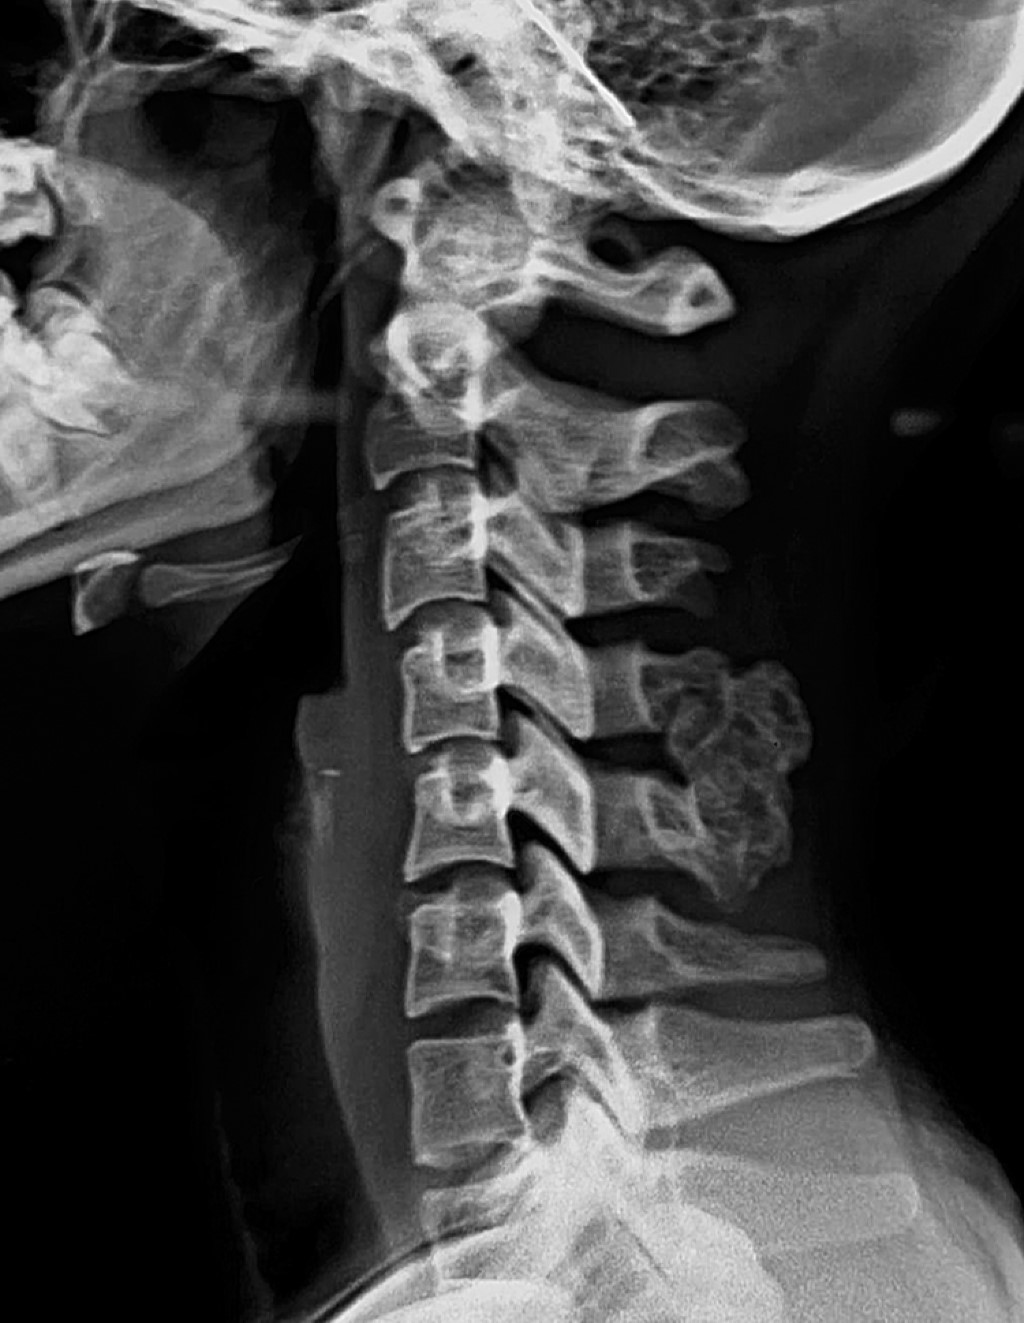

Spinal osteochondroma; overview and basic concepts

spine surgery, osteochondroma, chondrosarcoma, bone tumor, benign tumor, cervical spine.

Introduction: osteochondromas represent 10% of all bone neoplasms and 35% of benign bone lesions, making it the most frequent benign bone tumor; however, there is a low incidence of involvement in the spine, showing a greater predilection within the axial skeleton in the cervical segment. Osteochondroma is defined as an osteocartilaginous exostosis with cortical and medullary continuity contiguous to that of the bone of origin, the great majority presenting in its solitary form; however, a lower percentage of multiple affectations can also be observed as part of an autosomal dominant genetic pattern, mostly related to mutations of the EXT 1 and 2 genes. Diagnostic: the clinical presentation will depend on the location of the osteochondroma and the existence of some degree of compression to the spinal cord, being able to be detected in an incidental manner to the appearance of neurological symptoms. Multiple diagnostic tools are available, including radiography, computed axial tomography, and magnetic resonance imaging, visualizing it as an exophytic lesion with cortical and spinal cord continuity, however, the definitive diagnosis will be made using a pathology study. Treatment: the treatment will depend on the presence or absence of symptomatology and will be based on the total resection of the lesion to avoid recurrences.

Figure 1

Figure 2

Figure 3